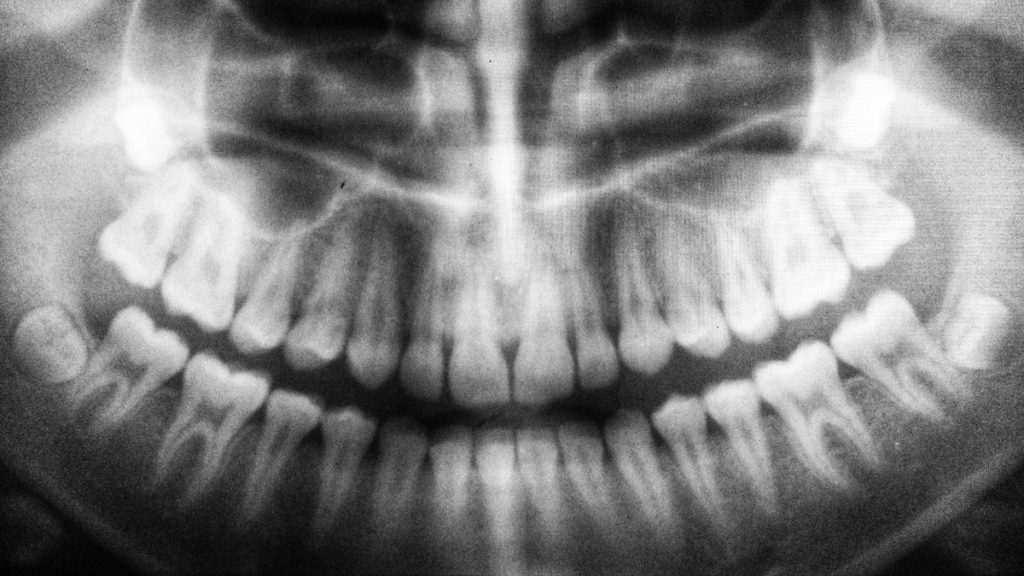

Las muelas del juicio, también conocidas como muelas cordales, son las últimas muelas en salir y se ubican justo al final de la boca en ambos lados de los maxilares. Existen cuatro muelas del juicio, y suelen desarrollarse entre los 16 y 20 años (aunque hay personas que las desarrollan mucho más mayores).

Sin embargo, no todas las personas desarrollan estas muelas, y cuando ocurre pero no hay suficiente espacio en la boca para que salgan, pueden ocasionar una serie de patologías que perjudican la salud dental.

La falta de espacio en la boca puede provocar que la muela del juicio no salga correctamente y, por tanto, produzca apiñamiento de otras piezas dentales adyacentes y maloclusión, es decir, un incorrecto alineamiento de los dientes. Cuando esto ocurre, lo más habitual es que los pacientes necesiten someterse a un tratamiento de ortodoncia.

Cuando las muelas no erupcionan correctamente, se pueden enquistar y provocar la desaparición de hueso mandibular.